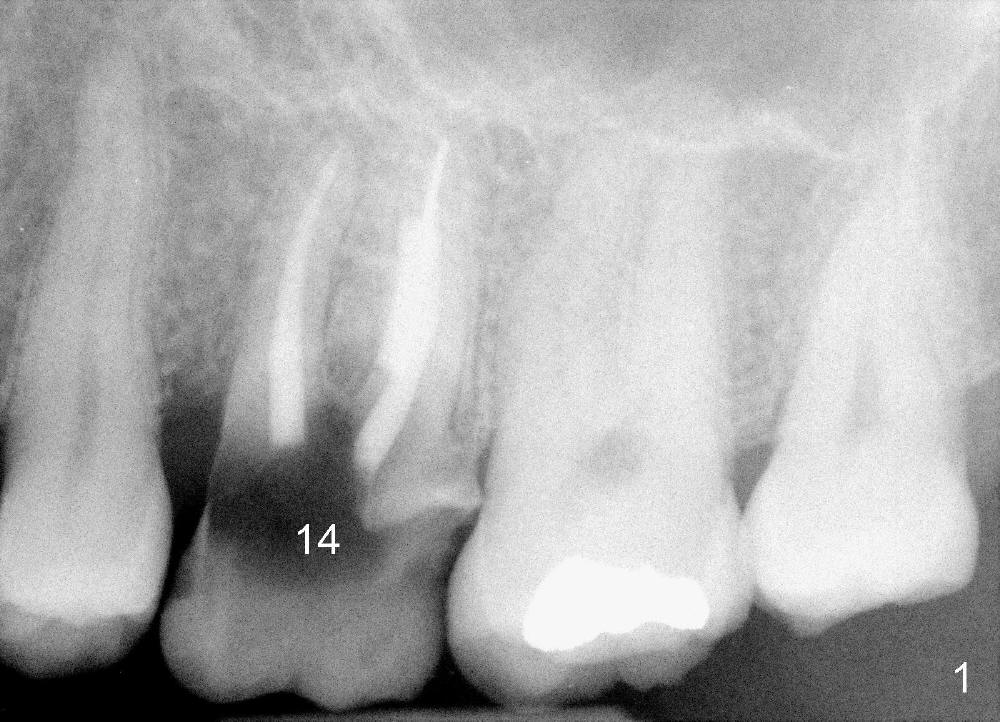

The 1st approach is used for the following case: a 46-year-old man with #14 (Fig.1). The root stumps are large and relatively close to each other (Fig.2 mirror view) so that when the roots are extracted (Fig.3 black), the septum is narrow (white). A 1.2 mm pilot drill penetrates the septum (red).

By the time a 2.6 mm bone expander is used, the septum starts to break off (Fig.4 green). The osteotomy site has to be changed: first to the palatal slope of the palatal socket (red) with the coronal end of the drill leaning buccally. Suddenly a better idea occurs: new osteotomy remains in the palatal socket, but as buccally as possible (blue) and finishes with rounded tapered osteotomes 2-4 mm at ~17 mm deep. The coronal end of the osteotomes is controlled to be positioned in the center of the socket (Fig.5 blue).